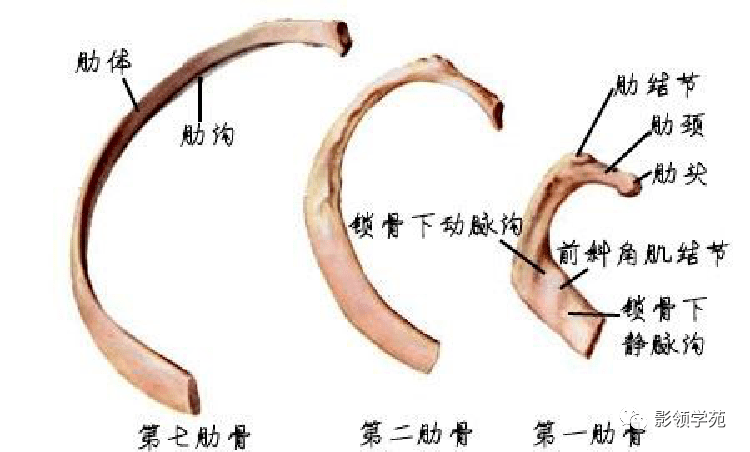

骨骼系统

骨骼系统